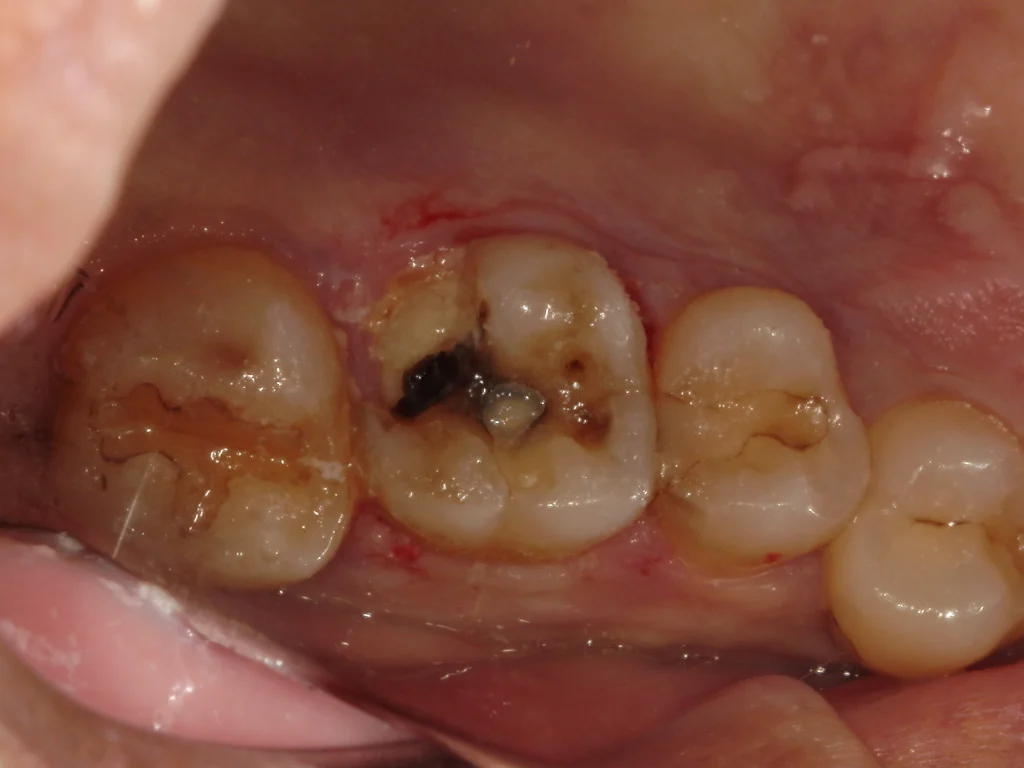

お久しぶりの歯医者さん、歯が欠けたとのことで来院、レントゲン検査にて右上奥歯に神経に達する大きな虫歯が見つかりました。

自発痛なく冷水痛が若干ある程度であったため、歯髄電気診を行なったところ神経が生きていることが確認できました。VPT歯髄温存療法の適応と判断し、ご本人様にその旨をお伝えしたところ、神経を残せる可能性があるなら試したいとのことでこの度VPT治療を行いました。

ラバーダム防湿を行い、丁寧に虫歯の除去を行う。

神経が出る位置まで虫歯が進んでいるため、一旦ここで虫歯除去を停止し壁を作っていきます。